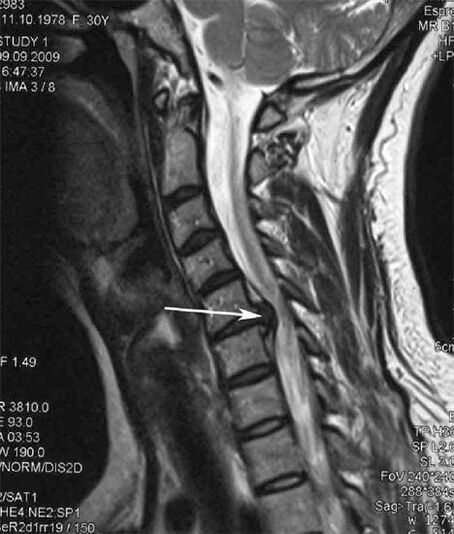

In the initial stages, MRI is used to detect osteochondrosis.Radiography can then be used to diagnose the pathology.On X-rays of the cervical spine, the distance between vertebrae decreases, pathological changes in the facet joints, and osteophyte hyperplasia become apparent.

Many people complain that they are unable to turn their necks due to severe pain after suddenly lifting heavy objects.This phenomenon indicates the formation of a herniated disc.Pain in the back, neck, and upper limbs is caused by a pinched nerve root in the spinal cord.

Do you have constant pain in your spine between your neck and shoulder blades?This may be a sign of the development of cervical osteochondrosis.Its pathological feature is the gradual destruction of the intervertebral disc nucleus, followed by herniation, hernia, spondyloarthropathy, and cervical spondylosis.